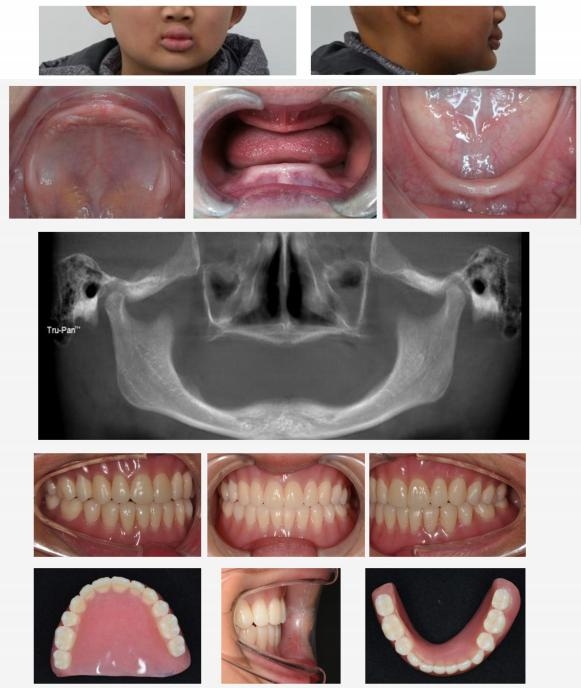

ED儿童通常在婴幼儿时期因汗腺发育不全而导致反复发烧,在牙发育期间,因牙胚部分甚至全部缺失而导致乳、恒牙无法萌出,使得面下部咀嚼功能受阻而导致发育不足,呈“瘪嘴 ”苍老面容,如头发稀少、卷曲,眉毛、睫毛稀缺,皮肤干燥,口周皮肤色素较深,上下唇呈外翻状。在影像学上呈现双侧颞下颌关节腔增大,牙胚缺失及牙槽骨、颌骨高度不足。

面容特征